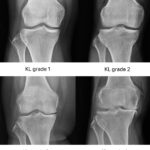

[doctormodu]1 knee OA KL grade stage X-ray

05 무릎 골관절염 Knee OA